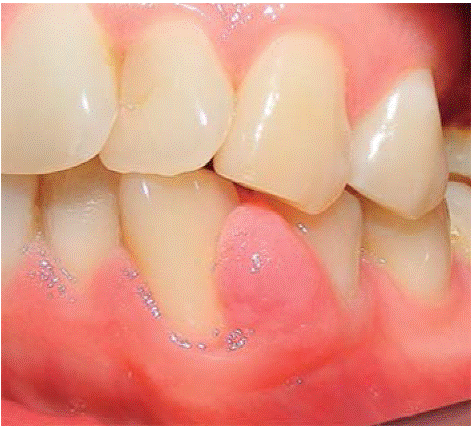

Al examen clínico se observa lesión gingival inflamatoria a nivel de las piezas 1.1 y 2.1, de aproximadamente 9 X 9 mm, cubriendo un tercio de la corona clínica, de consistencia firme, lobulada, textura rugosa, sangrante ante el estímulo y asintomática (Figura 9). A la evaluación periodontal no presentaba bolsas periodontales, sin embargo, se observó presencia de placa, obteniéndose un índice de higiene oral (O'Leary) de 50%.

Al examen radiográfico se observó alteración de la cresta ósea entre las piezas 1.1 y 2.1 (Figura 10).